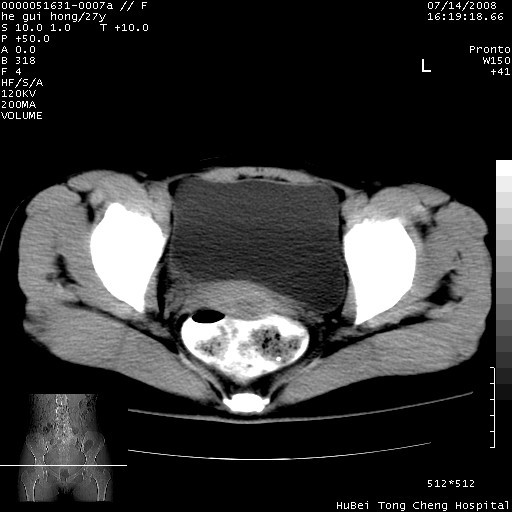

以下是引用杀毒软件在2008-7-20 8:03:00的发言:[br]支持双侧卵巢囊腺瘤可能性大!

以下是引用zjzjr在2008-7-20 13:36:00的发言:[br]双侧附件囊腺瘤可能性大!